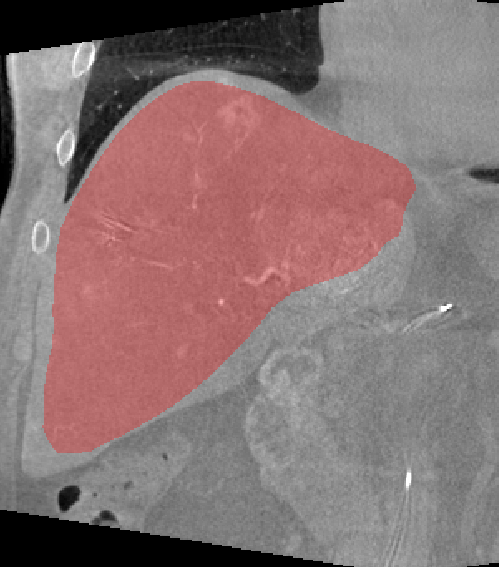

Figure 3: The result of multi-organ segmentation of a CT dataset (left), an example of the liver segmentation of a flat-panel CT scan of a liver (middle) and the warped visible human phantom overlay with a CT (right).